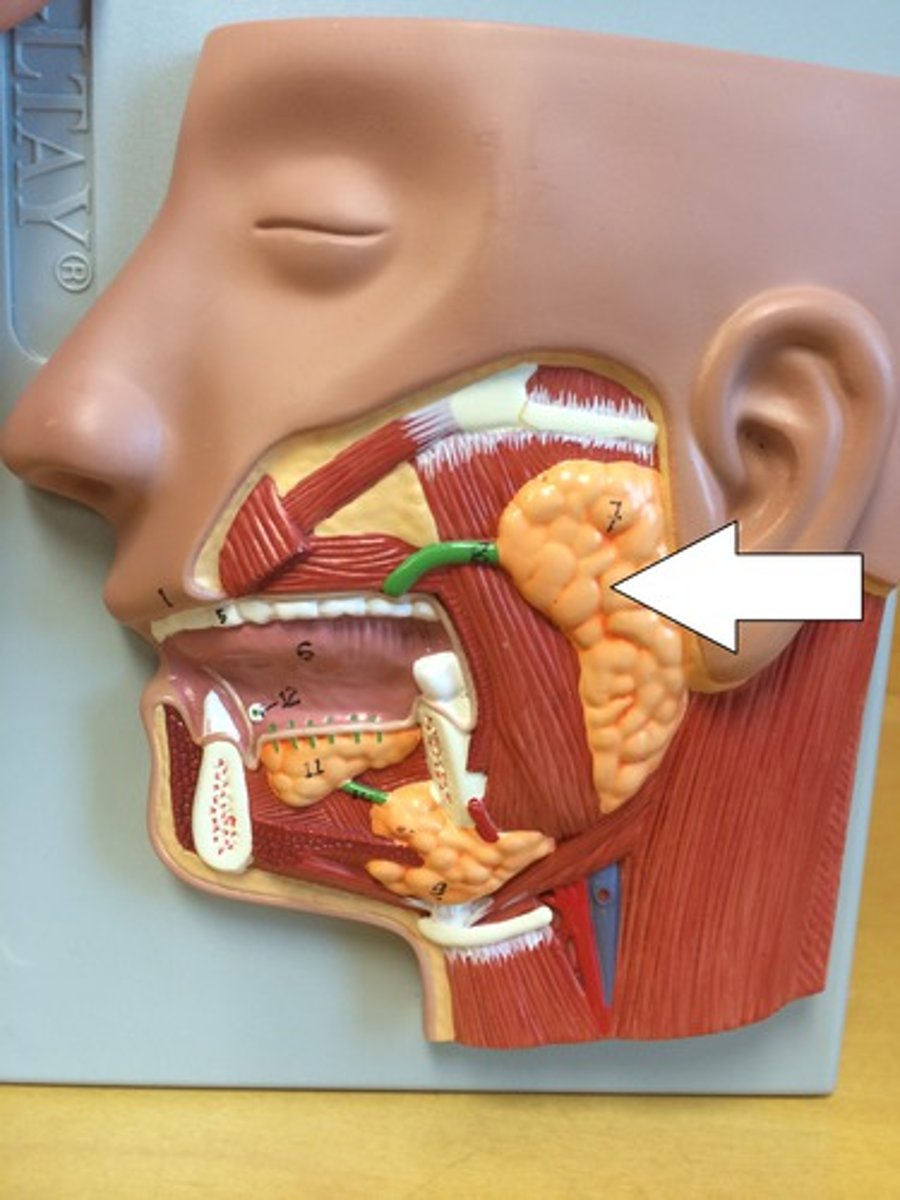

Parotid salivary glands